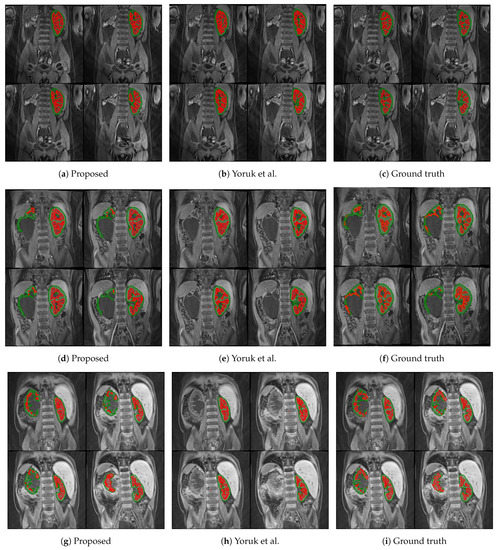

The first columns of Figure 5 and Figure 6 display the medulla (red) and cortex (green) segmentation results in four coronal slices from a single DCE-MRI scan depicting clinically “normal” and “abnormal” kidneys, respectively. Using contrast enhancement via gamma correction and sigmoidal transformation maintained the contextual information while differentiating kidney regions; this occurred mainly in temporal instances where the contrast between DCE-MR imaged renal compartments was low but enough to capture boundary differences where the medulla and cortex edges were in contact.

Figure 6.

Medulla and cortex segmentation results of three different clinically “abnormal” kidneys. The first column (a,d,g) shows the results from the proposed approach; the second column (b,e,h) shows the respective results using the baseline approach from Yoruk et al. [16]; the third column (c,f,i) shows the respective ground truth.

The proposed renal segmentation approach outperforms a baseline method [16] for extracting the medulla and cortex by approximately 9.3% and 17.1% in mean DSC, respectively, and it boasts higher statistical stability by approximately 15.7% and 12.4%, as shown in Table 3. An available implementation [34] is utilised to reproduce the baseline method. Whereas the baseline method utilises computer vision to extract the whole kidney, the approach proposed in this report employs advancing deep learning to predict highly diverse kidney features, especially of abnormalities. As shown in Figure 6e,h, the algorithm in [16] fails to detect one of the clinically “abnormal” kidneys, whereas the proposed approach has accurately identified the entire organ, as illustrated in Figure 6d and Figure 6g, respectively. Moreover, the baseline approach completely breaks down in a clinically “normal” case, as shown in Figure 5e. In contrast, the robustness of the deep-learning-based model captures both kidneys before renal segmentation is performed, as shown in Figure 5d. A limitation of this particular case (Figure 5d) includes a relatively higher false-negative cortex prediction, resulting in a higher false-positive medulla compared to the ground truth in Figure 5f. Therefore, thresholding parameters would require optimisation to ensure a more robust generalisability. Thus, it would be helpful to expand upon nature-inspired algorithms such as the firefly and swarm intelligence algorithms to determine multilevel thresholds and enhance the compartment segmentation efficiency. In Figure 5h, the binary dilation and erosion strategy in the baseline approach predicts false-positive labels of renal parenchyma, whereas the proposed trained deep learning model accurately localises the kidney. Furthermore, the relatively high concentration of false-negative medulla labels demonstrates the limitations of incorporating the GrabCut and SVM classifier, as in [16]. In comparison, the proposed renal segmentation method exploits intensity enhancement throughout the full temporal dimension of the DCE-MRI to generate the “optimum” medulla labels for the resultant segmentation, as highlighted in Figure 5g.